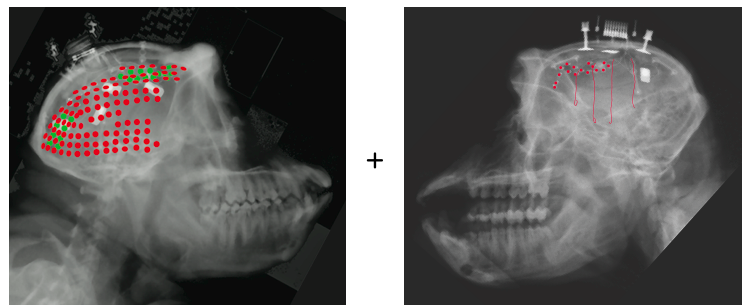

center